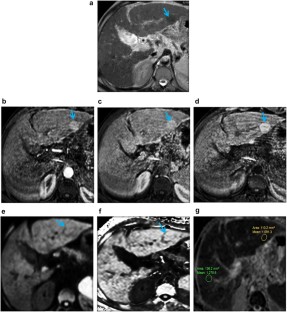

Fig. 1

Fig. 2

Fig. 3

Fig. 4